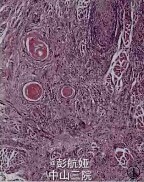

左上唇皮肤微囊性附属器癌1例

患者女性,41岁,因发现左上唇唇红上缘肿物2年余入院,肿物略高于皮肤表面,颜色稍红无疼痛、破溃,口内外双合诊,可扪及一2.5cm*2cm*1cm肿物,质地较硬,边界不清,不活动,无触痛。行左上唇病灶扩大切除术,术后抗炎治疗。